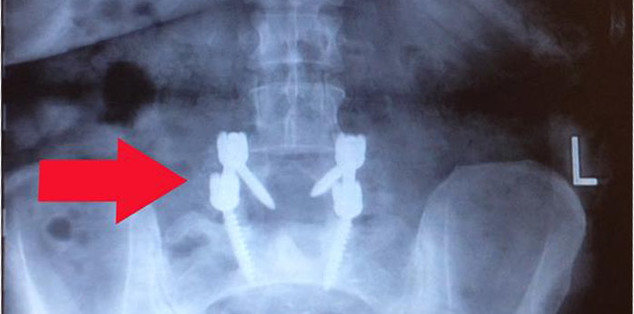

I had back pain for quite awhile. At first it was manageable, but it gradually got worse. I had gone from having to sit down frequently while shopping to using a walker and eventually to using a motorized scooter to even go to the grocery store. Someone suggested that I see what the doctors had to say at Rothman. I made an appointment at the King Of Prussia location. The doctor there managed to get me an appointment for an MRI for which my PC had not been able to do. I was called shortly after the results and told I should see Dr. Rihn in Media on August 15th. On August 28th I was scheduled for surgery to correct my spine I had a severe slip. Dr. Rihn was an excellent surgeon and made sure I knew exactly what was going to happen and what it all entailed.